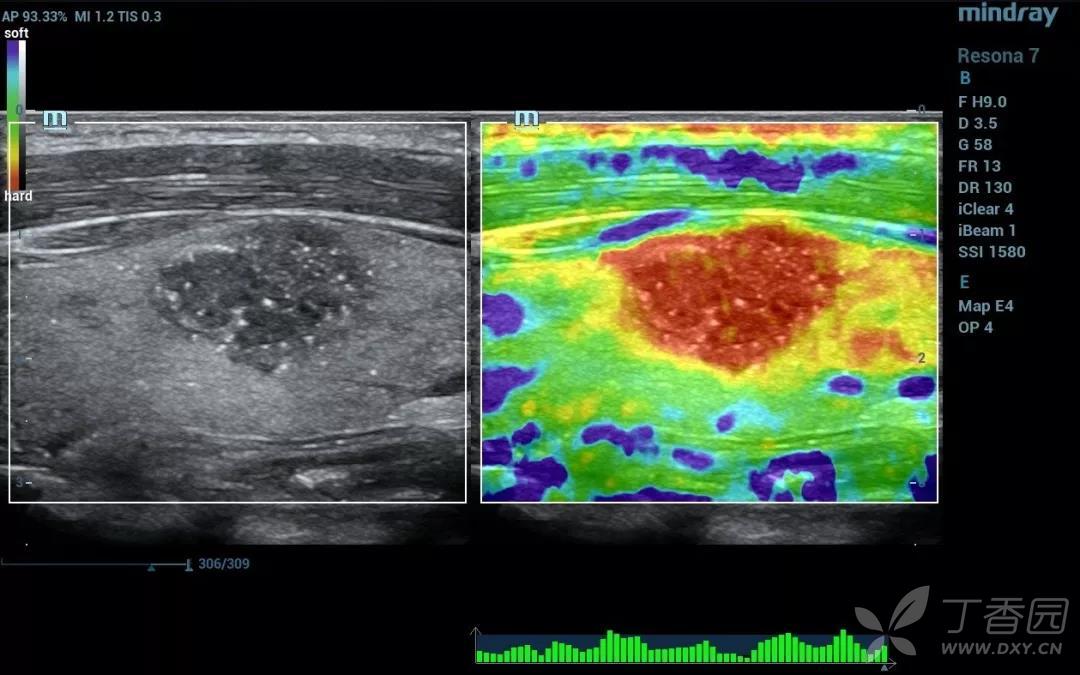

双模态弹性成像

顿悟:一文读懂乳腺超声弹性成像